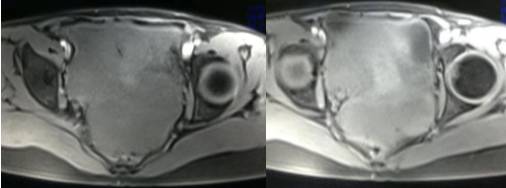

MR检查:

病理结果:黄体血肿

根据时间不同MR信号也有所不同,TIWI脂肪抑制序列可以鉴别脂肪和出血。

卵巢囊腺瘤:呈囊性或囊实性肿块,边界清楚,壁厚,有分隔或结节( 直径≤3mm) ,浆液性囊腺瘤:囊液呈T1WI 低信号,T2WI 高信号,黏液性囊腺瘤呈T1WI 高信号、T2WI 稍高信号,T2WI 信号高于水,信号较均匀,增强扫描囊壁及壁结节强化。

畸胎瘤:多呈囊性或囊实性,单房或多房状,囊内液体可有分层,实质由多胚层组织构成,MR 信号不均,肿块内见脂肪信号有利于畸胎瘤的诊断。

巧克力囊肿:常呈多发的单囊或多囊改变,病灶大小不等,囊壁厚薄不均,囊内信号复杂,囊内或各囊腔间血液因出血时期不同,信号常呈多样性,囊肿内反复出血、破裂,形成相互粘连的多房性囊肿,是其较为特征性的表现。

在鉴别卵巢畸胎瘤、出血性囊肿或巧克力囊肿时,MR 脂肪抑制T1WI 可明确肿块内高信号成分是脂肪还是出血,同时由于脂肪组织与非脂肪组织的共振频率不同,在两者交界处沿磁场频率编码方向出现化学位移伪影,但出血性囊肿与巧克力囊肿的鉴别有时较为困难。